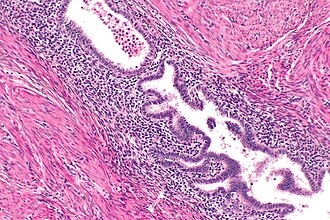

Uterine adenomyosis. H&E stain. | |

| LM | at least 2 of 3: (1) endometrial glands, (2) endometrial stroma, (3) hemosiderin-laden macrophages |

Microscopic

Features:

- Endometrial glands within uterine muscle - key feature.

- Endometrial glands:

- Circular.

- Simple epithelial or pseudostratified epithelium +/- mitoses.

- +/-Surrounded by endometrial stroma.

- Densely packed spindle cells without nuclear atypia.

- Blood:

- Within glands.

- Hemosiderin-laden macrophages.